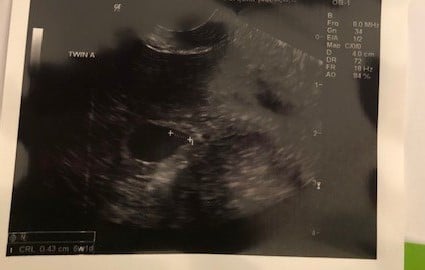

Found out yesterday, I am having twins.. EDD 12.7.19